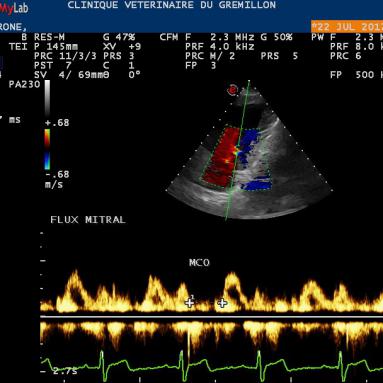

IPM: Indice de Performance Myocardique (Methode dite des flux)

Pour effectuer sa mesure, il est necessaire de mesurer le temps entre deux flux mitraux et de le temps d'ejection systolique

La fraction d'ejection systolique par la methode volumétrique, c'est la methode de simpsons. Elle complète la mesure FE calculée à partir du TM